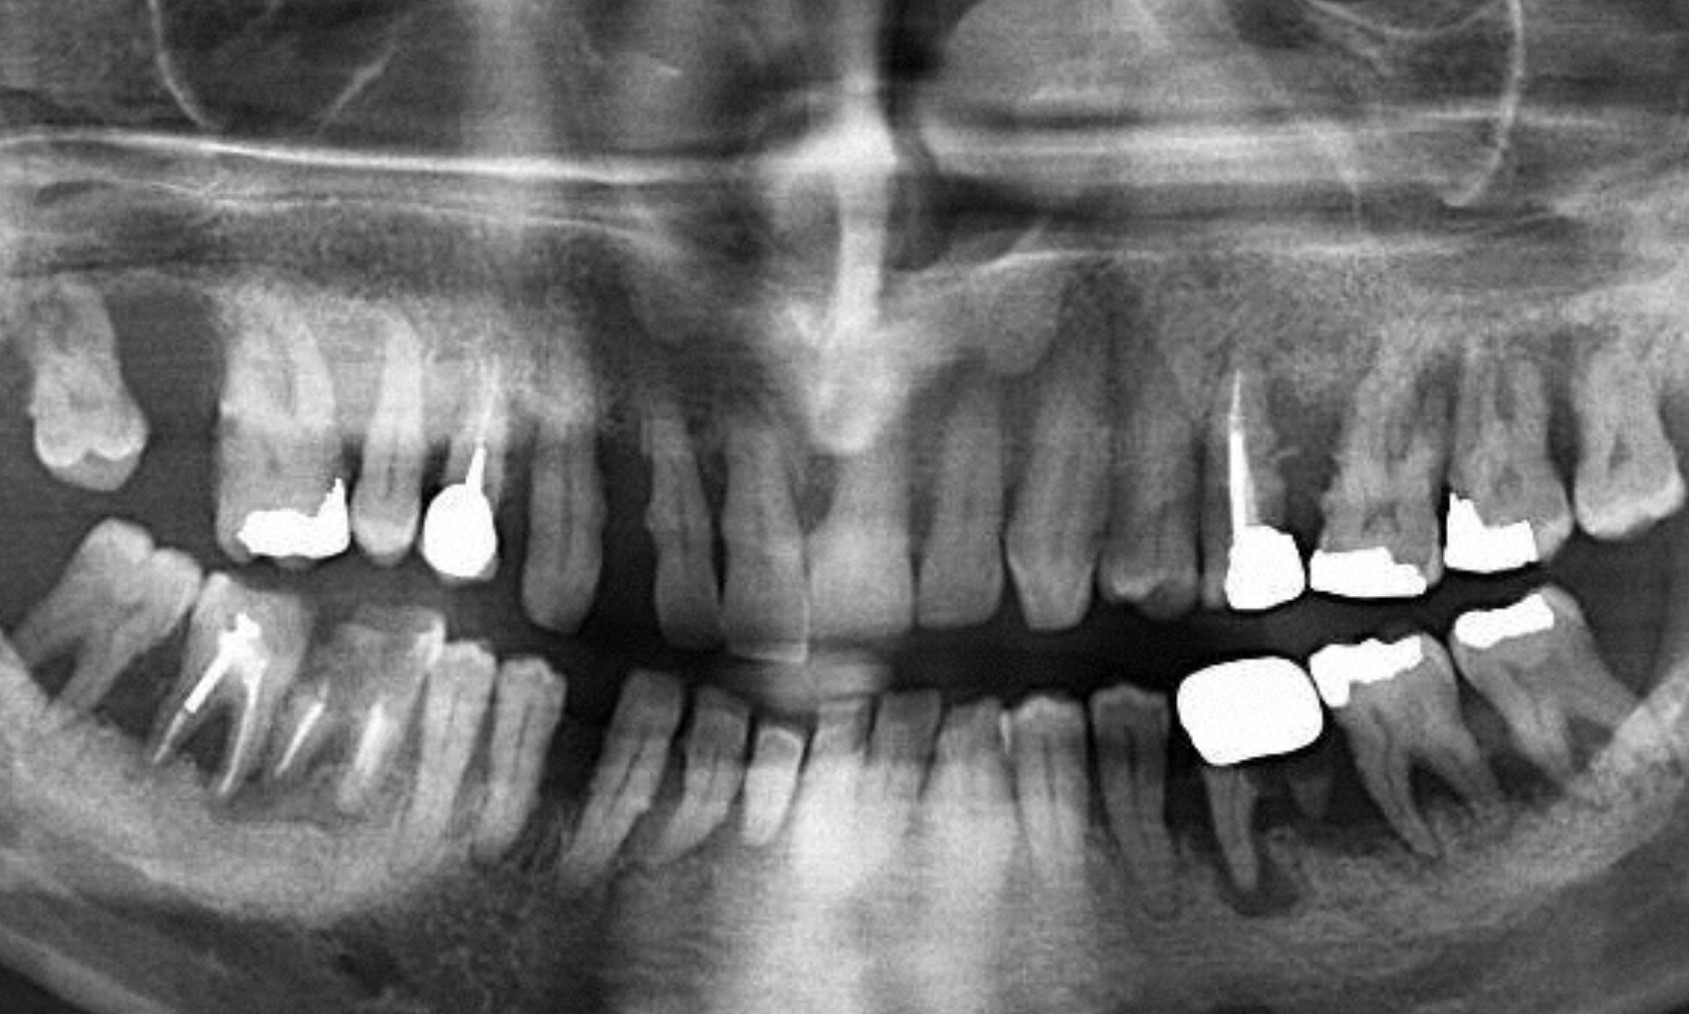

גלריית הצגת מקרים לפני ואחרי